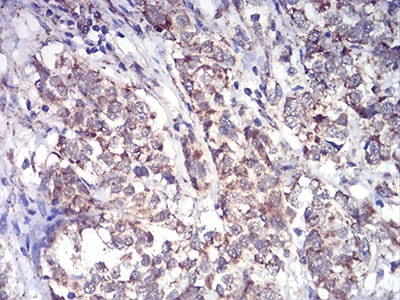

Immunohistochemical analysis of paraffin-embedded human ovarian cancer tissues using ALDH6A1 mouse mAb with DAB staining.